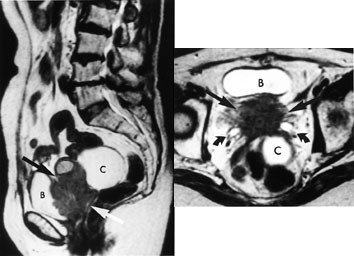

T2-vektede bilder fremstiller tre soner i corpus uteri (fig 11). Den indre sonen (endometriet) har meget høyt signal, mens den ytre sonen (myometriet) har middels høyt signal. Overgangssonen mellom disse fremtrer som et bånd med lavt signal. Den representerer den innerste delen av myometriet, der cellene ligger tett sammenpakket med sparsom ekstracellulær matriks (14). Utseendet til corpus uteri varierer med fasen i menstruasjonssyklus og med andre hormonelle stimuli.

Cancer cervicis uteri

Tumor fremstilles tydelig på T2-vektede bilder (fig 12). Størrelsen er den viktigste faktor for prognosen, og MR gir god informasjon om denne (15). MR kan dertil påvise infiltrasjon til parametrier, bekkenvegg, blære og rectum samt affeksjon av urinledere. Siden den kliniske stadieinndelingen er usikker, har MR stor betydning i primærutredningen, spesielt ved store svulster.